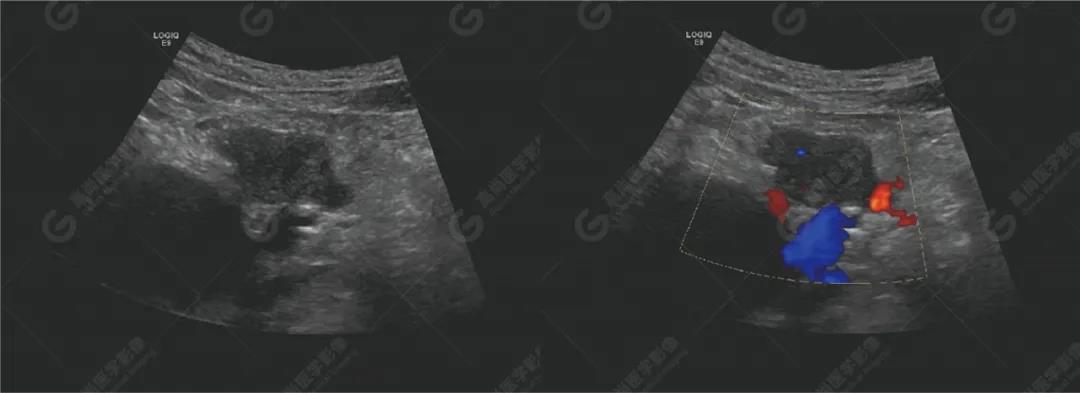

超聲檢查

超聲檢查所見:胰腺形態(tài)不規(guī)則,胰頭探及兩個實性低回聲團(tuán),大小分別約48mm×22mm、30mm×23mm,邊界不清,形態(tài)不規(guī)則,內(nèi)回聲欠均勻,CDFI顯示內(nèi)部可見少許血流信號。主胰管無擴(kuò)張。